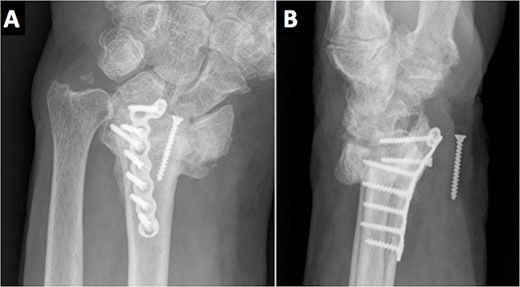

Due to the comminuted fracture and the bone osteoporosis, the final decision was closed reduction and fixation with K-wires. Due to the inadequate reduction, we decided to associate an external fixator. However, during surgery, an inadequate reduction of the ulnar column was observed, and thus, a mixed synthesis with an L-shaped plate was added (Fig. 2).

On the third month of follow-up, the loosening of the second most distal screw was observed on plain X-rays. Six months after surgery, radiographic controls showed a migrated screw lodged in the anterior aspect of the wrist. Moreover, the patient complained of anesthesia on the median nerve distribution of the hand (Fig. 3). No motor deficits or atrophy of the thenar eminence were noted. A standard electromyography (EMG) was performed resulting in a complete axonotmesis of the median nerve. During the following 8 months, the patient did not attend the follow-ups. Upon his next follow-up visit, the hypoesthesia on the radial three digits persisted despite the fact that no muscular atrophy or motor deficits were observed, as in his last clinical examination. A new EMG was performed again confirming complete median nerve axonotmesis, and with proximal stimulation, a Martin–Gruber anastomosis in the proximal forearm was discovered [4]. The patient refused further surgery for screw removal.